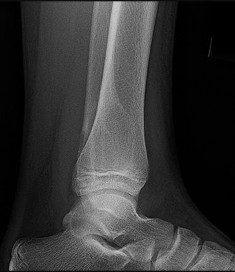

Figures 9a through 9d are the anteroposterior and lateral radiographs, CT scan, and technetium bone scan of a 12-year-old boy who has experienced 7 months of pain in his lower leg. The pain limits his ability to participate in sports and he is having difficulty sleeping. He is afebrile, and laboratory study findings including an erythrocyte sedimentation rate, C-reactive protein, and complete blood count are within normal limits.

The images and clinical history support a diagnosis of osteoid osteoma, which most commonly occurs in adolescence. Although these lesions can be seen in any bone, they are usually located in the femur and tibia. The significant inflammatory response to this tumor is secondary to high levels of prostaglandin production. Characteristic night pain is relieved with nonsteroidal anti-inflammatory drugs (NSAIDs) or by aspirin.

Radiographic images show thickened bone and a small central nidus. Thin-cut CT scan is the imaging of choice to visualize the nidus. A bone scan is associated with uptake but is not specific. Treatment options include expectant management with NSAIDs and observation under the premise that these lesions eventually burn out. Contemporary treatment involves RFA. Historically, these lesions were treated with en bloc resection; however, this technique has largely fallen out of favor because of the high efficacy and comparative low morbidity associated with RFA.

When an osteoid osteoma occurs in the spine, it is located in the posterior elements, and paraspinal pain and scoliosis often are present.